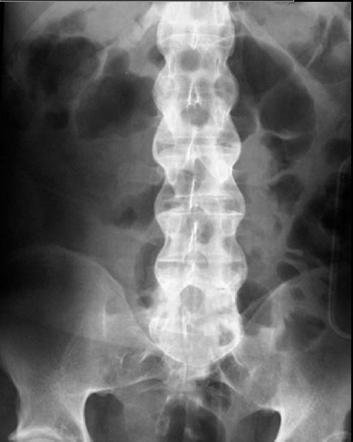

Wervelfractuur

Traumatisch of spontaan

Rugpijn ontstaan na val bij oude vrouw.